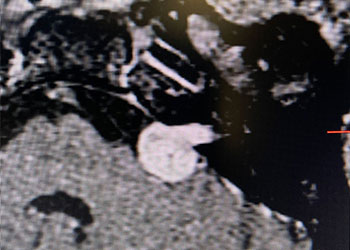

Nomenclature: While these tumors are generally referred to as “acoustic neuromas”, it is understood that these are generally, in reality, “vestibular schwannomas”. The tumor arises from […]